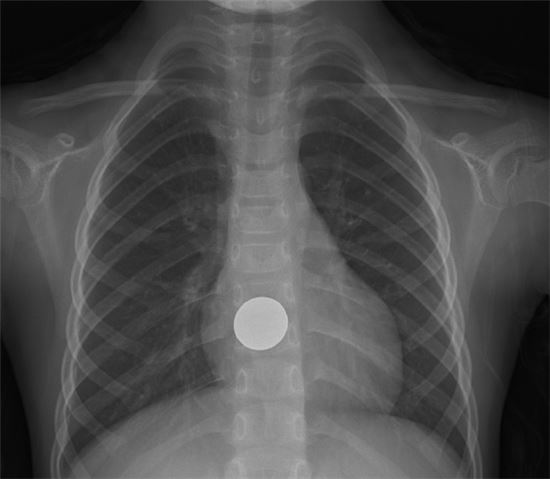

이물의 크기와 종류, 위장관 내 위치와 머문 시간에 따라 이물 제거 시기와 방법은 다릅니다. X-ray 검사로 대략적 이물의 위치나 크기, 모양을 확인할 수 있습니다. 생선 뼈, 닭 뼈, 고기 등 음식물을 비롯해 유리, 알루미늄, 플라스틱, 나무로 만든 이물 등은 X-ray 검사에 잘 나타나지 않기 때문에 추가 내시경 검사가 진단 겸 치료에 도움이 됩니다.

날카로운 물체가 위나 근위 십이지장에 있다면 내시경으로 제거하는 것이 좋습니다. 십이지장 만곡부를 통과한 이물은 좀 더 지켜봐야 합니다. 배터리나 날카로운 물질이 식도에 있을 때는 즉시 내시경으로 제거해야 합니다. 배터리는 식도에 걸려 있는 채로 4시간 이상 지나면 궤양, 천공, 누공 등의 합병증을 초래할 위험이 있습니다. 동전 등 둔탁한 물질은 식도에 있더라도 24시간 이내에 제거하는 것을 권하고 있습니다. 위에 위치한 이물이 날카롭거나 뾰족한 경우와 배터리가 48시간 이상 머물렀거나 2개 이상의 자석은 금식 후 내시경으로 제거해야 합니다.